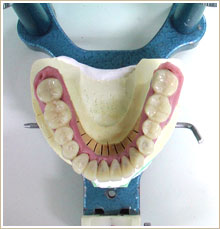

来院時の写真を見ると下顎の前歯が長くアンバランスなのが分かります。

これは噛み合わせが高過ぎるために生じています。治療後の写真と比較すると明かです。